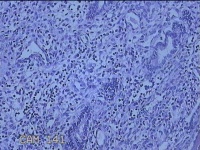

宫腔内容物

性别

女

年龄

47岁

临床诊断

1.异常子宫出血 2.慢性宫颈炎

一般病史

不规则阴道流血21天。

标本名称

大体所见

灰白暗红色不规则碎组织2.5x1.8x0.3cm一堆。

图1